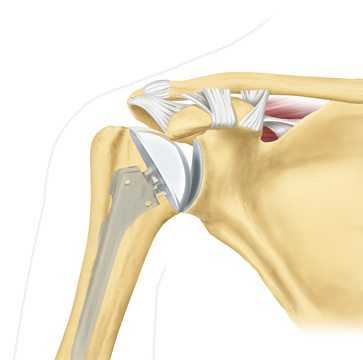

Общее описание остеоартроза плечевого сустава

Остеоартрозом поражаются практически все структуры плечевого сустава — субхондральная кость, связки, капсула, синовиальная оболочка, периартикулярные мышцы. Но первым повреждается хрящ. Он становится менее прочным и эластичным, постепенно истончается и уплощается. Изменение состояния хрящевой прослойки приводит к утрате ей амортизационной способности. Теперь она не снижает ударные нагрузки, возникающие при сгибании или разгибании сустава.

Нередко течение заболевания осложняется воспалительным процессом. Поэтому его называют артрозо-артритом. Воспаление тканей, разрушение хряща становятся причиной разрастания костных тканей с образованием острых наростов — остеофитов.